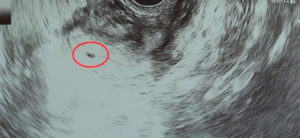

Расшифровкой данных ультразвукового исследования должен заниматься только квалифицированный специалист. На первом УЗИ специалист определяет:

- Наличие каплевидного или округлого гипоэхогенного образования, диаметр которого составляет 0,3-0,5 см. От срока зависит и размер.

- Образование должно быть окружено тонкой оболочкой. Данное образование и есть плодное яйцо.

- Наличие желтого тела.

Во время первого УЗИ обнаруживаются:

- круглое или каплевидное образование с низкой эхогенностью размером 3-5 мм. Его размер определяет срок;

- тонкая оболочка вокруг развивающегося ребёнка;

- жёлтое тело – оно вырабатывает прогестерон, способствующий сохранению плода.